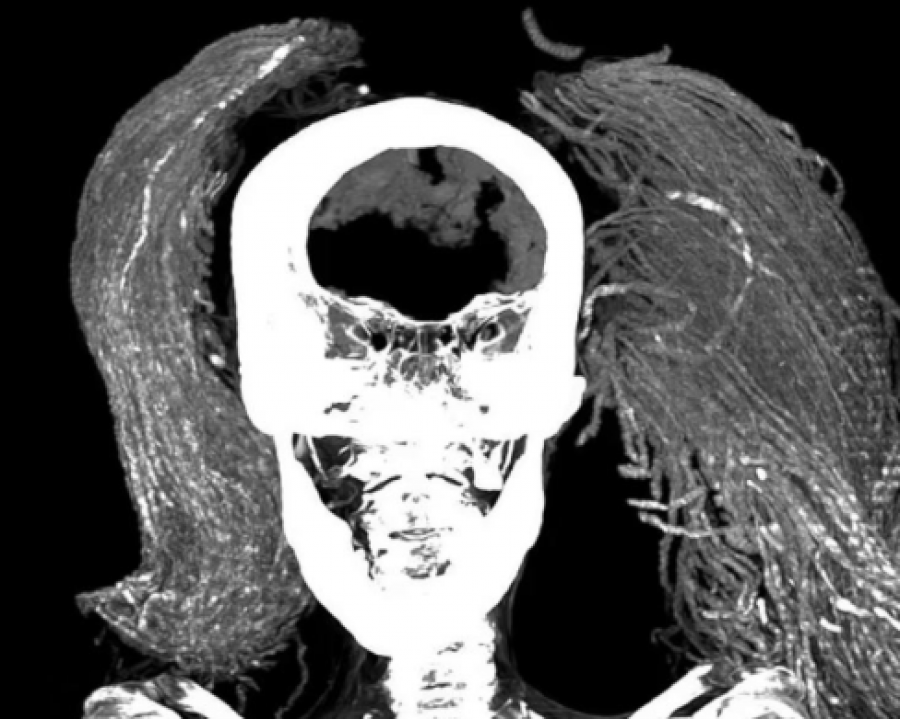

3.500 yıl önce yaşamış bir Mısır mumyası, araştırmacıların dikkatini çekti. "Çığlık Atan Kadın" olarak adlandırılan bu mumya, ölüm anında acı içinde çığlık atarken donup kalmış gibi görünüyor. 1935'te keşfedilen mumya, siyah peruk ve değerli yüzükler taşıyan bir kadına ait. Bilim insanları, en son teknolojileri kullanarak mumyayı inceledi.

Araştırmalar, kadının 48 yaşlarında, 1.54 metre boyunda olduğunu ve hafif omurga artriti yaşadığını gösterdi. Mumyalama işleminde pahalı malzemeler kullanılmış, bu da kadının önemli biri olabileceğini düşündürüyor. Dr. Sahar Saleem, kadının yüz ifadesinin "kadavra spazmı" olabileceğini belirtti. Bu, şiddetli ve acı dolu bir ölümü işaret ediyor.

İlginç bir şekilde, o dönemin mumyalama geleneğinin aksine, kadının iç organları çıkarılmamış. Bu durum, mumyanın neden ve nasıl bu halde kaldığı konusunda yeni sorular doğuruyor. Frontiers in Medicine dergisinde yayımlanan bu çalışma, eski Mısır'daki yaşam ve ölüm hakkında yeni bilgiler sunuyor. Ancak "Çığlık Atan Kadın"ın ölüm nedeni hala gizemini koruyor.